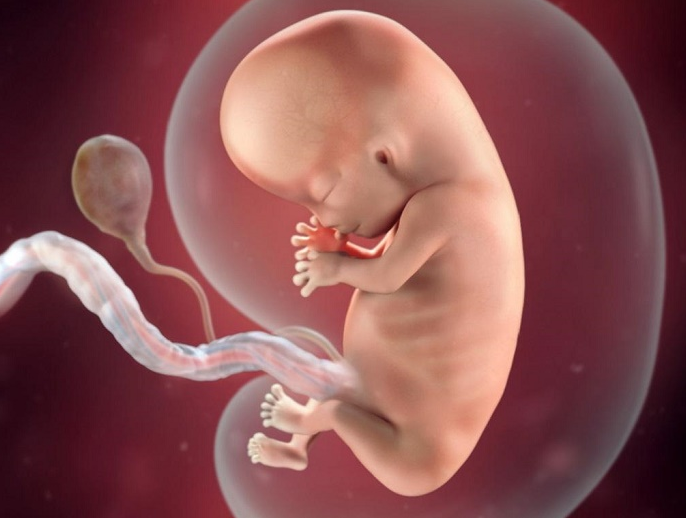

Trong giai đoạn thai tuần thứ 7, phôi thai và túi thai còn quá nhỏ nên khó nhìn thấy. Tuy nhiên, đây cũng là những tuần giữa trong tam cá nguyệt thứ nhất. So với tuần đầu tiên, bé cũng có sự phát triển rõ ràng nhất vào tuần này. Cụ thể là:

Tim thai bắt đầu hình thành khi thai 5 tuần tuổi. Lúc này tim thai chỉ gồm các ống dẫn đơn giản với kích thước rất nhỏ, chỉ bằng hạt gạo. Sang tuần thai thứ 7, tim thai đã lớn hơn, chia thành buồng tim phải và trái. Tim thai sẽ tiếp tục phát triển và hoàn thiện cho tới tuần thứ 12 - 14 thì tim bắt đầu đập mạnh mẽ. Lúc này, mẹ có thể nghe thấy nhịp tim thai rõ ràng thông qua các thiết bị hỗ trợ.

Tim thai được hình thành rất sớm, thường xuất hiện vào khoảng tuần thứ 6 hay ngày thứ 16 của thai kỳ. Đến tuần thứ 7 của thai kỳ, nhịp tim thai nhi lớn dần lên và bắt đầu phân chia thành hai buồng trái và phải, đã xuất hiện hai mạch máu ở phôi thai, hình thành hai ống dẫn vào tim thai. Mẹ có thể nhìn thấy và đo được những điểm sáng nhấp nháy trên màn hình của máy siêu âm.

Dù hình dáng thai nhi chưa hoàn thiện vào lúc này, nhưng tim thai lại được hình thành và co bóp tốt, đập như quả tim người. Cuối tuần thứ 5 của thai kỳ là một cột mốc quan trọng, nếu thấy tim thai chứng tỏ một mầm sống đã trỗi dậy.